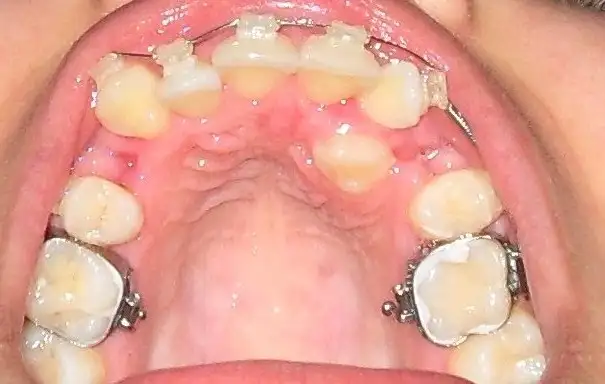

İlklerden olayım dedim.benim tedavim başlayalı 10 gün oldu.çoook yeni çünkü ortalama sürem 2,5 seneymiş.beni yalnız bırakmayın sizde ekleyin. $11.webp $15.webp :29:

İlklerden olayım dedim.benim tedavim başlayalı 10 gün oldu.çoook yeni çünkü ortalama sürem 2,5 seneymiş.beni yalnız bırakmayın sizde ekleyin.Eki Görüntüle 188683 Eki Görüntüle 188684 :29:

geçmiş olsun canım resimler için teşekkürler bende devamlı ekliyorum resim aşağı yukarı aynı gibi dişlerimiz benim 4 ay bitti 5 aya girdim köşeli tel taktı bana dişleri ileri itmek için inatçılar gitmiyorlar yerlerine :(